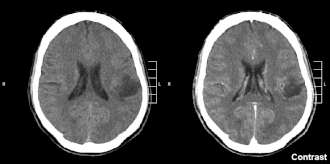

| Glioma no lobo parietal de segundo grau em CT scan cerebral. | |